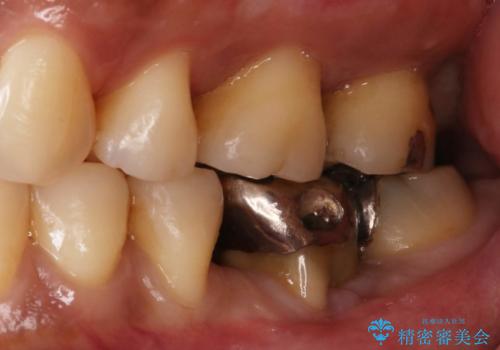

見えない歯周病 長期予後を見据えてインプラントに

- Ⅲ度の分岐部病変をきたした第1大臼歯を抜去、待時しインプラントによる咬合回復を計画した。

奥歯の根の又の部分の歯周病(=分岐部病変)が進行してしまった場合、

・掃除をしながら様子をみる

・歯の形態を修正し清掃性の向上をはからう

・歯を分割し小臼歯形態×2で補綴する(確定外科が必要)

・より病変の影響を強く受けている方の根だけ抜去し、残った根を温存する

など多様な治療の選択肢があります。

ケースによりますが、いずれの場合も不安要素をかかえたまま歯を温存することになるため、それらを取り除く・かつ感染源を取り除くために歯を抜去するのも効果的な治療法といえます。